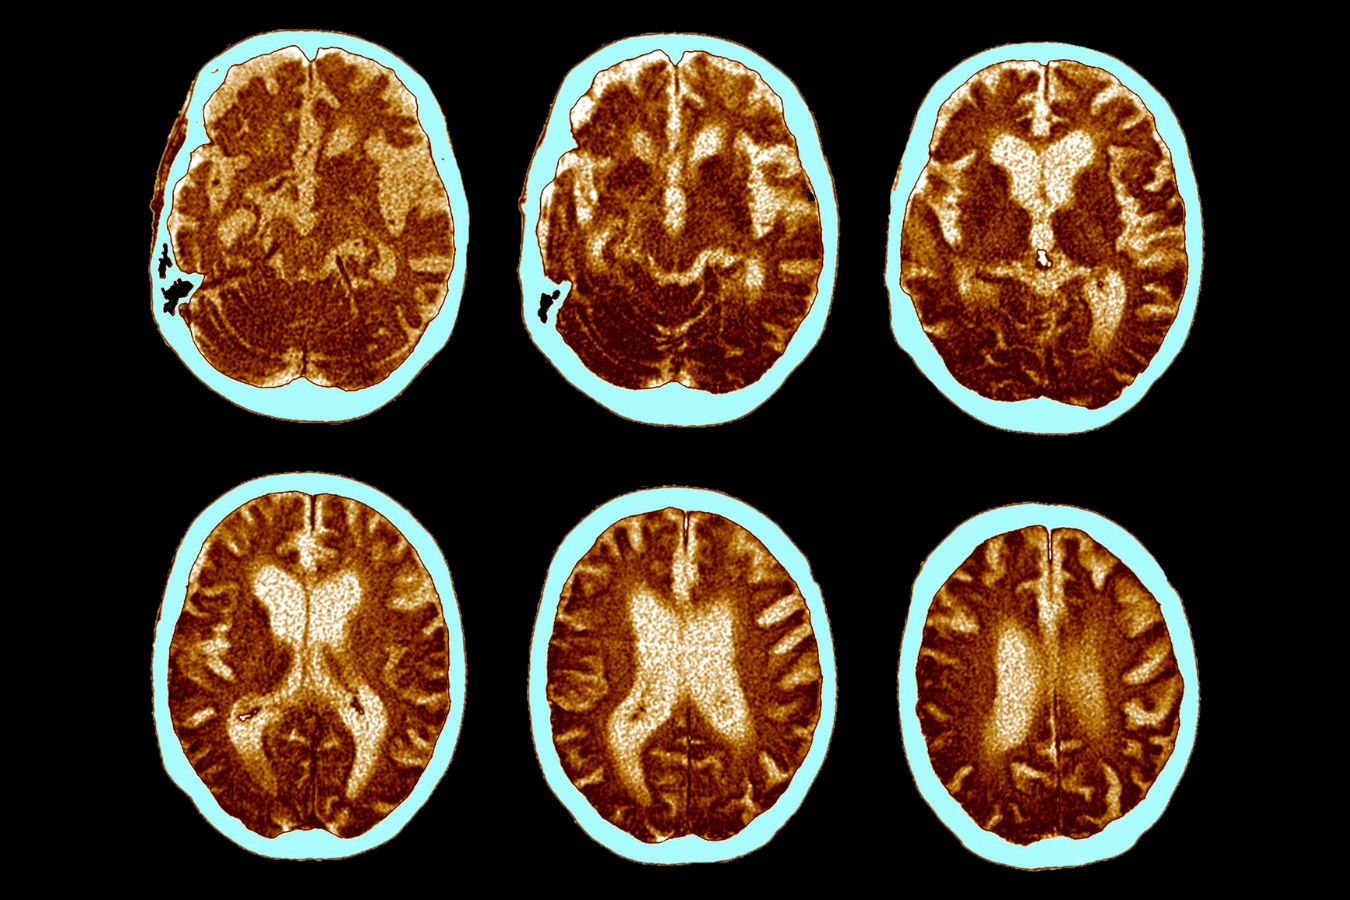

알츠하이머

치매, 알츠하이머병에 대한 줄기세포 치료

알츠하이머병에 적용한 줄기세포 치료의 매커니즘: 줄기세포는 손상된 뇌의 신경세포를 재생시키고, 염증을 줄이며, 신경계의 기능을 회복시키는 데 도움을 줍니다. 또한, 줄기세포는 뇌 내의 베타-아밀로이드 플라크와 타우 단백질의 축적을 줄이는 데 기여하여 신경세포의 손상을 방지합니다.

줄기세포 치료는 알츠하이머병의 근본적인 문제를 해결하는 데 중점을 둡니다. 줄기세포는 손상된 신경세포를 재생시키고, 새로운 신경세포로 분화하여 뇌 기능을 회복시킵니다. 또한, 줄기세포는 항염증 작용을 통해 뇌 조직의 염증을 줄이고, 베타-아밀로이드 플라크와 타우 단백질의 축적을 감소시킵니다